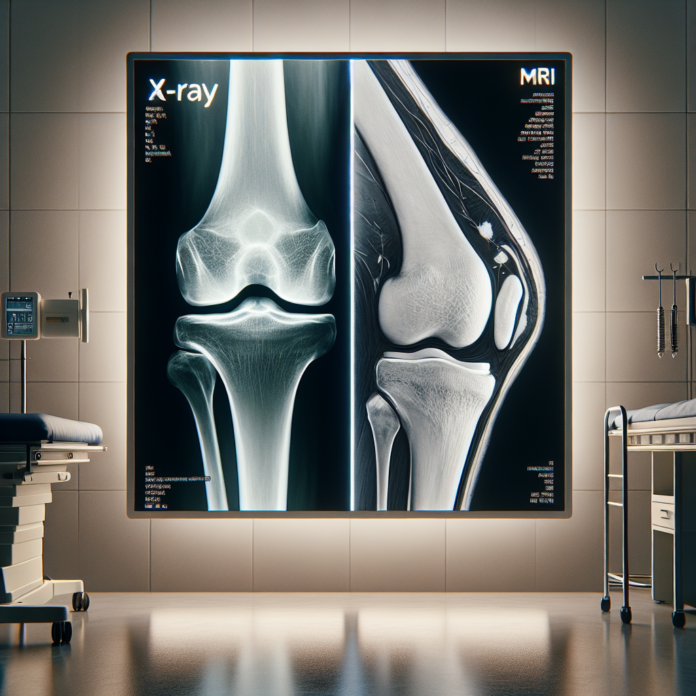

X-rays are a staple in the world of medical imaging due to their ability to paint a clear picture of the bone structure. They excel in visualizing bones and can effectively show the bone spacing that indicates the presence of cartilage. This characteristic makes X-rays particularly useful in identifying osteoarthritis, as it often manifests as a narrowing of the joint space due to cartilage loss. Here’s what X-rays can show when assessing osteoarthritis:

- Bone Structure: X-rays provide a detailed view of the bones, making it easier to identify deformities and the development of bone spurs—an indicator of advanced osteoarthritis.

- Joint Space Narrowing: The space between bones on an X-ray is a proxy for cartilage thickness. A narrowing of this space signals cartilage wear, a hallmark of osteoarthritis.

- Bone on Bone Contact: Weight-bearing X-rays, performed in many orthopedic offices, can show the extent of bone on bone contact. This is a crucial indicator of the severity of arthritis, which can be better visualized under the influence of gravity and body weight.

However, X-rays have limitations. They only show the bones and do not provide information about the meniscus, ligaments, or detailed cartilage condition.

Magnetic Resonance Imaging (MRI), on the other hand, offers a more comprehensive view of the joint’s internal structures. This includes not just the bones, but also the soft tissues like cartilage, ligaments, and tendons. An MRI can detail the specific areas where cartilage may be thinning or has been breached, offering a comprehensive assessment of joint health. Here’s what MRIs add to the diagnosis of osteoarthritis:

- Cartilage Condition: MRIs can visualize the thickness and health of articular cartilage, revealing specific areas of thinning or damage that X-rays cannot show.

- Soft Tissue Evaluation: They provide detailed images of all soft tissue components within the joint, such as ligaments and tendons, helping to identify any concurrent injuries or conditions.

- Detailed Assessment Without Weight Influence: While lying down during an MRI might underestimate arthritis severity due to the absence of body weight, it can nonetheless reveal the presence of minute cartilage defects and other abnormalities.